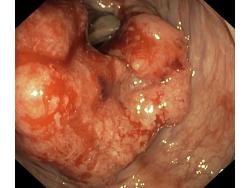

Nowotwory przewodu pokarmowego